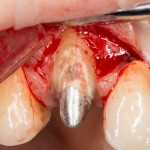

Ключевой семинар по использованию биоматериалов в имплантологии, остеопластических операциях, мукогингивальной хирургии и хирургической пародонтологии. Я спланировал семинар как ответ на главный вопрос: «Почему нам вообще нужны биоматериалы, и можем ли мы без них обойтись?» В ходе семинара подробно рассмотрены основные методики регенерации костной ткани, начиная от пластики крупными аутокостными фрагментами, заканчивая направленной костной регенерацией, с имплантами или без.

Как видно из названия, семинар посвящен самой частой и распространенной хирургической операции в мире — удалению зубов. Это новое мероприятие в моем графике, мы проводим его совместно с IDA (International Dentistry Association). В ходе семинара будут рассмотрены различные методики удаления зубов, в том числе удаление ретинированных зубов мудрости, сверхкомплектных зубов, а также операции, включающие в себя эту процедуру: немедленная имплантация и превентивная аугментация лунок.

Это мой самый любимый и тщательно подготовленный проект — семинар по немедленной имплантации. Он уже дважды был в Москве, и однажды — в Нижнем Новгороде. На этот раз, мы проводим его совместно с компанией APEX в Санкт-Петербурге, и посвящен он будет… догадайтесь с трех раз?))) Через фокус немедленной имплантации будут рассмотрены различные имплантационные системы, операции остеопластики, синуслифтинга, удаления зубов и превентивной аугментации лунок.